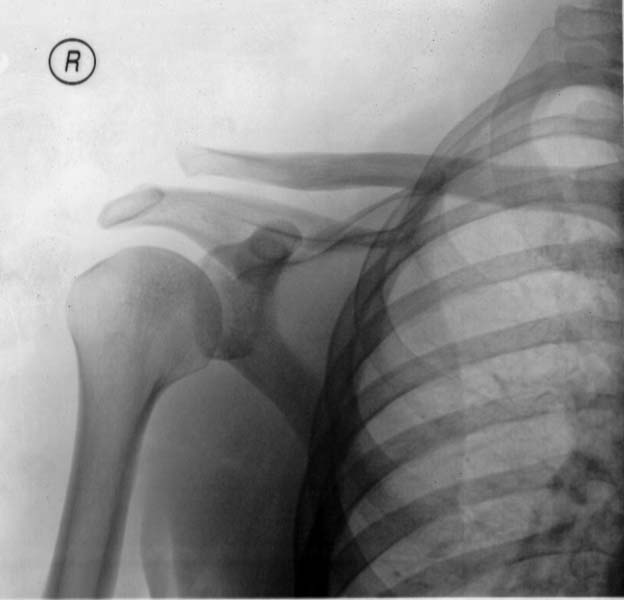

X Ray Of Separated Shoulder . A health care provider inspects the affected area for tenderness, swelling or deformity and checks for signs of nerve or blood vessel. A shoulder separation occurs when a fall or other trauma tears or stretches the ligaments of your acromioclavicular joint, which is the point.

A shoulder separation occurs when a fall or other trauma tears or stretches the ligaments of your acromioclavicular joint, which is the point. A health care provider inspects the affected area for tenderness, swelling or deformity and checks for signs of nerve or blood vessel.